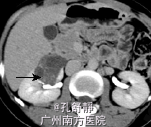

入院后查血肌酐为158umol/L,移植肾功能良好。腹部CT提示右肾巨大占位性病变,且分隔,考虑右肾肾癌。

诊断:右肾占位性病变,考虑右肾肾癌 处理:检查提示肾癌可能性大,跟患者和患者家属讨论后决定手术治疗,于是在入院后第3天在我院行右侧肾癌根治术,术后取活检确诊为肾癌,术后结合化疗。